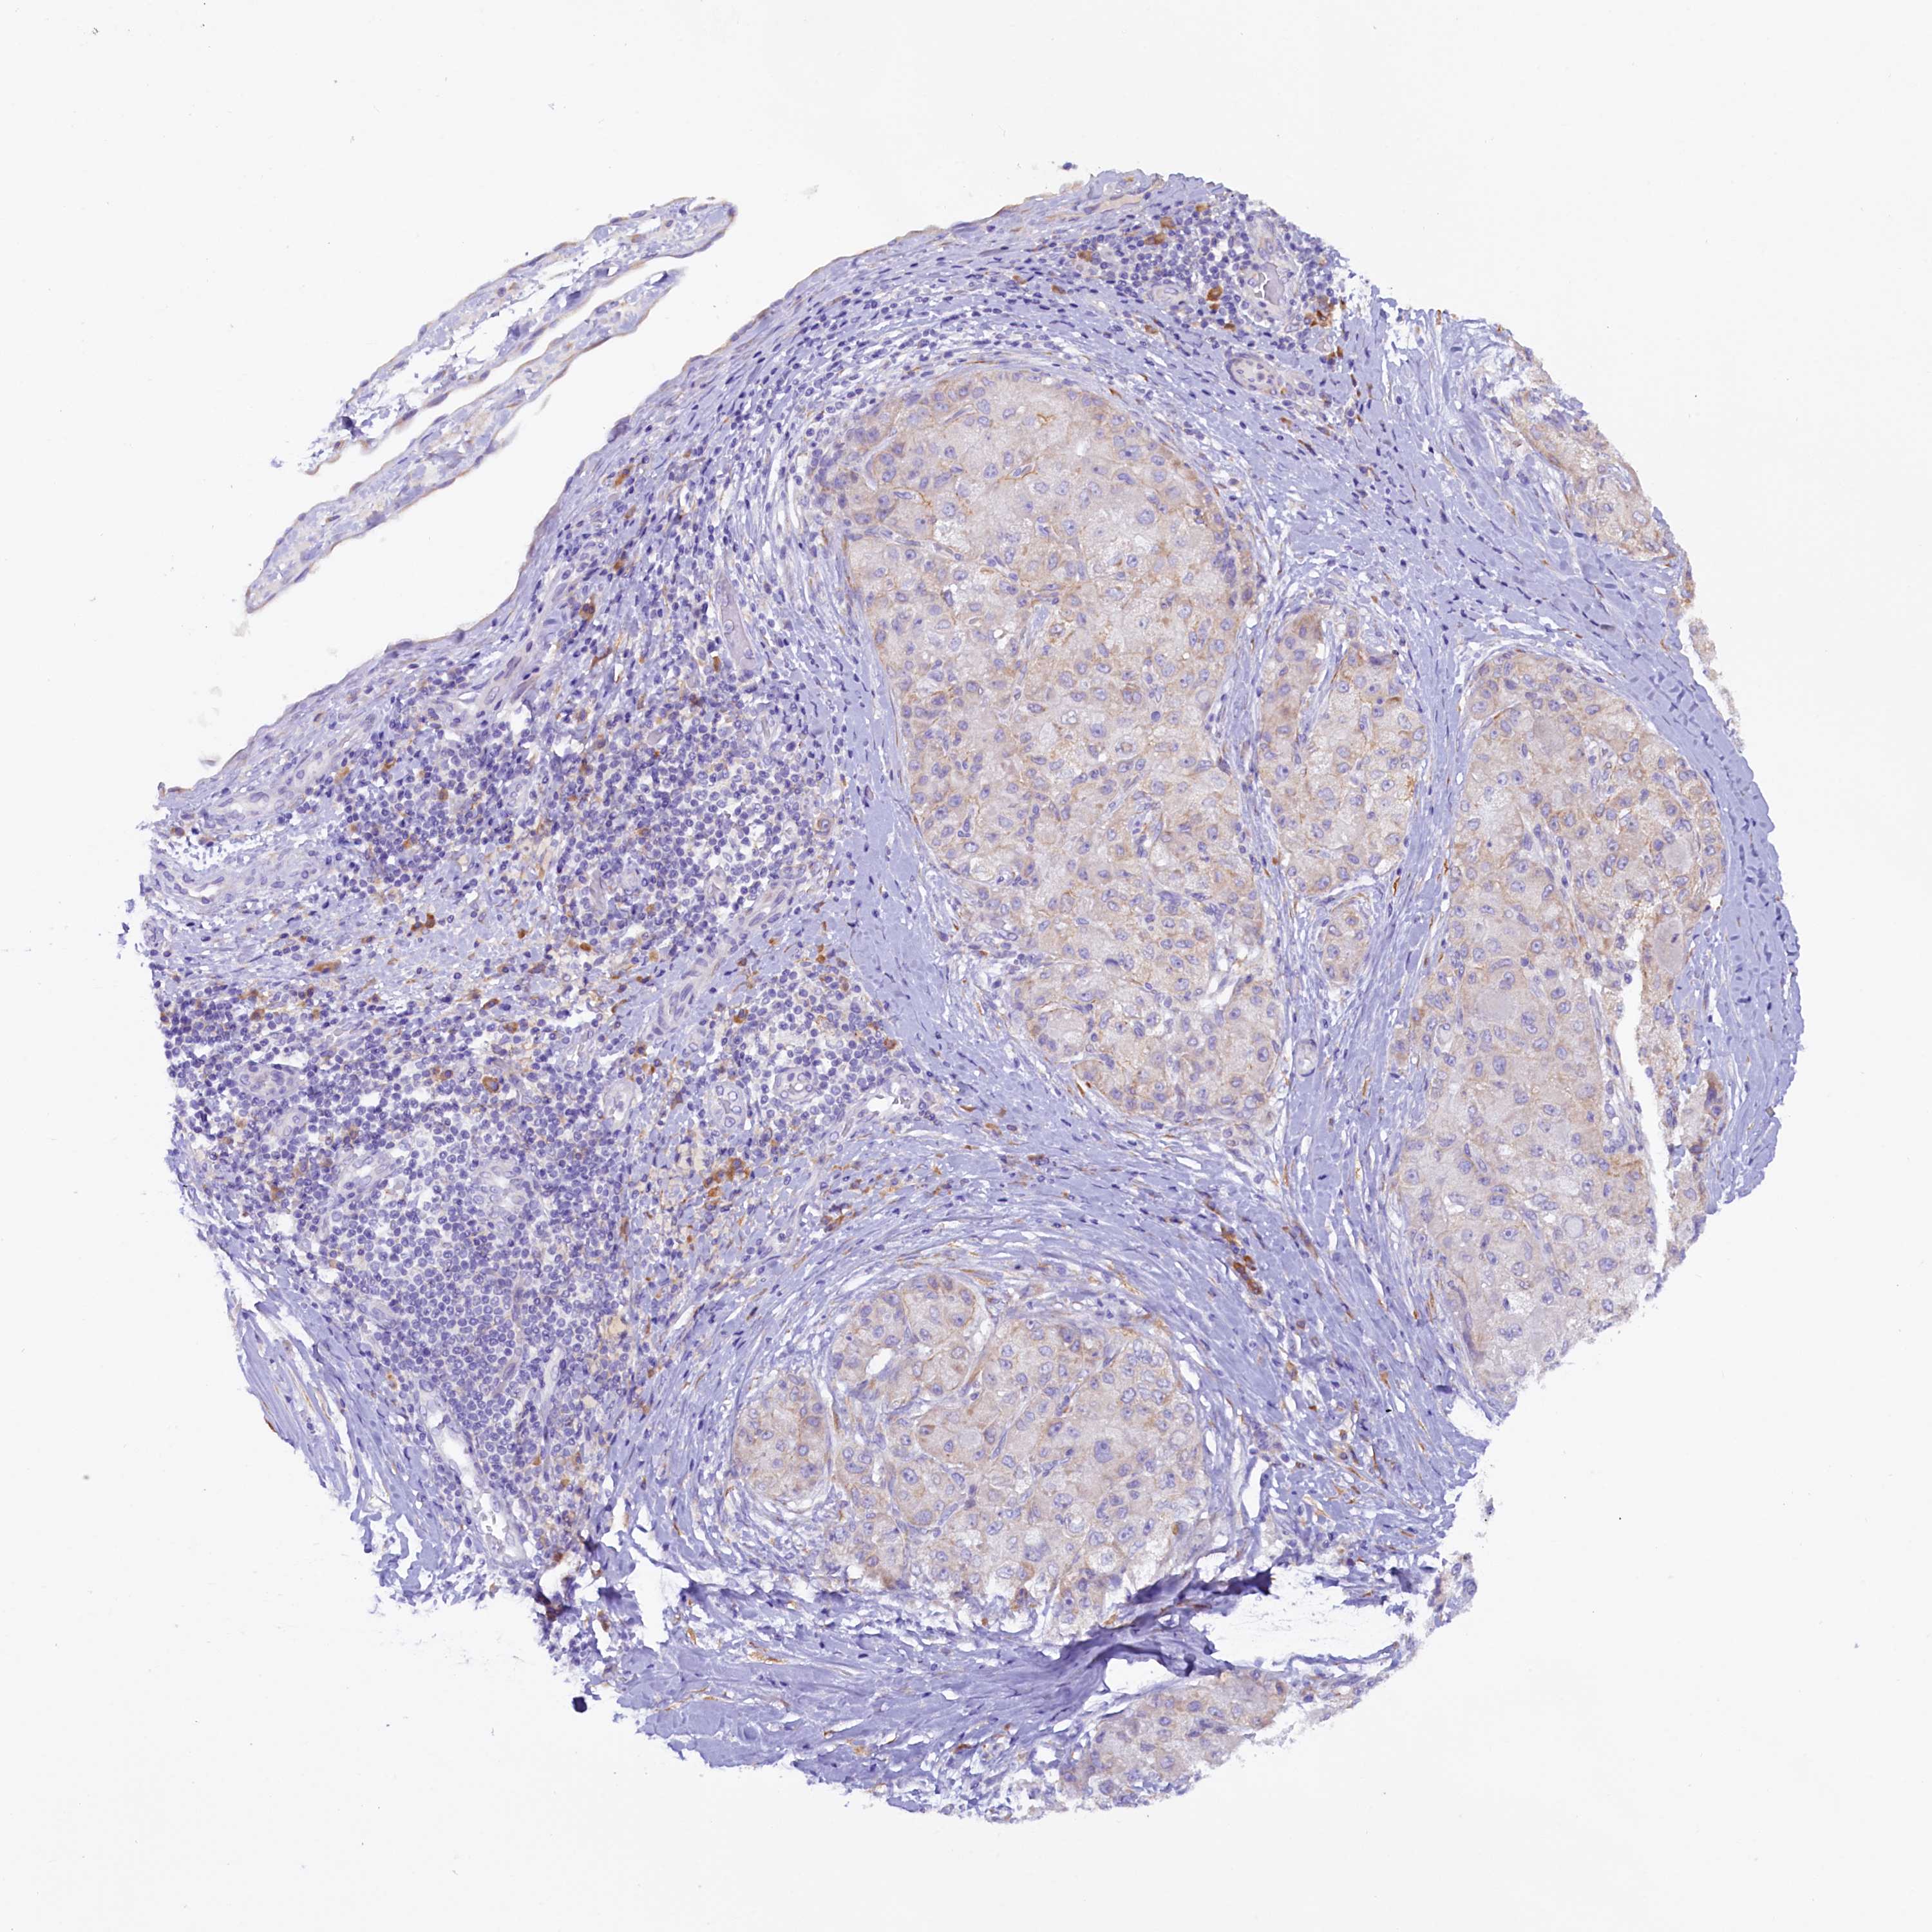

LIVER CANCER - Protein expressioni

A mouse-over function shows sample information and annotation data. Click on an image to view it in a full screen mode. Samples can be filtered based on level of antibody staining by selecting one or several of the following categories: high, medium, low and not detected. The assay and annotation is described here.

Note that samples used for immunohistochemistry by the Human Protein Atlas do not correspond to samples in the TCGA dataset.

Antibody stainingi

Antibody staining in the annotated cell types in the current human tissue is reported as not detected, low, medium, or high, based on conventional immunohistochemistry profiling in selected tissues. This score is based on the combination of the staining intensity and fraction of stained cells.

Each image is clickable and will lead to virtual microscopy that enables deeper exploration of all samples and also displays staining intensity scores, fraction scores and subcellular localization as well as patient and tissue information for each sample.

Antibody HPA042008

Staining

High

Medium

Low

Not detected

Intensity

Strong

Moderate

Weak

Negative

Quantity

>75%

75%-25%

<25%

None

Location

Nuclear

Cytoplasmic/membranous

Cytoplasmic/membranous,nuclear

Cholangiocarcinoma

Carcinoma, Hepatocellular, NOS